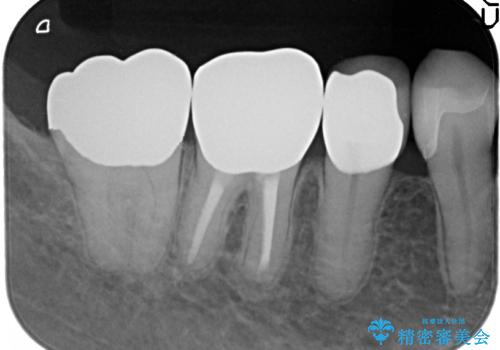

- 右下の古い銀歯のやり替えを希望された方の症例です。

口腔外から見えやすい 4 番目、5 番目の歯はセラミックによる審美的な治療を行い、6 番目、 7 番目の奥歯 2 歯は適合性に優れたPGA(ゴールド)クラウンによる治療を行いました。

- PGAクラウン…¥80,000×2、オールセラミッククラウン…¥100,000、仮歯…¥10,000×3、ファイバーコア…¥20,000、セラミックインレー…¥70,000費用は治療当時の料金となります